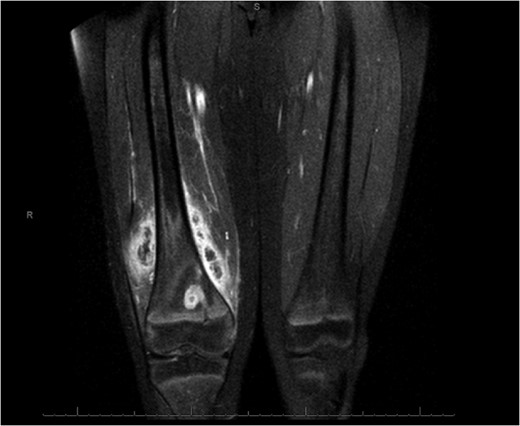

Coronal slice images of presenting MRI, displaying the brodie's abscess and collection.